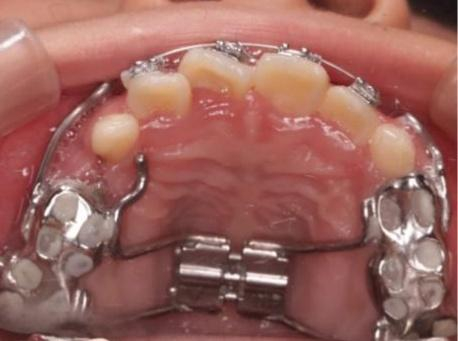

正如大家所了解的,在正畸医生的帮助下,七扭八歪的牙齿能排列得整整齐齐,变得“好看又好用”。经过口腔检查,结合拍的X线片,你需要拔4颗牙才能正畸。

01 为什么需要拔牙矫正?

随着饮食逐渐精细,人类颌骨适应环境首先退化缩小,而牙齿数量或大小并未发生明显变化,这就导致了现代人颌骨逐渐容纳不下牙齿,牙齿不齐、龅牙等问题产生。

为了解决骨量小于牙量这一核心问题,正畸医生需要想方设法增大骨量或/和减少牙量,目标在牙弓中创造出间隙,以实现牙列的排齐和“龅牙”的内收。

扩大牙弓周长以匹配牙量,包括唇倾前牙、扩弓、磨牙远移等。

减少牙齿总宽度以匹配骨量(就是我们常说的拔牙哦)。